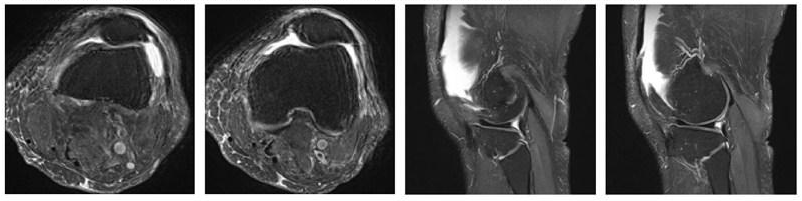

1、核磁共振图像(MRI)

核磁共振成像(Magnetic Resonance Imaging, MRI)是一种非侵入式的活体成像技术,科学将其定义为处于静磁场中的原子核在另一交变电磁场作用下发生的物理现象。通常人们所说的核磁共振就是利用核磁共振现象获取分子结构,以及人体内部结构信息的技术。共振成像的基本原理,是将人体置于特殊的磁场中,用无线电射频脉冲激发人体内氢原子核,引起氢原子核共振并吸收能量,在停止射频脉冲后,氢原子核按特定频率发出射电信号,并将吸收的能量释放出来,被体外的接受器收录,经电子计算机处理获得图像。

核磁共振成像技术提供的信息量不但大于医学影像学中的其他许多成像术,而且不同于已有的成像术。因此,它对疾病的诊断具有很大的潜在优越性。它可以直接作出横断面、矢状面、冠状面和各种斜面的体层图像,并且不会产生CT检测中的伪影;不需注射造影剂;无电离辐射,对机体不良影响较小。共振成像对检测脑内血肿、脑外血肿、脑肿瘤、颅内动脉瘤、动静脉血管畸形、脑缺血、椎管内肿瘤、脊髓空洞症和脊髓积水等疾病非常有效。同时,对腰椎椎间盘后突、原发性肝癌等疾病的诊断也很有效。

当然,共振成像也存在不足之处。它的速度相对较慢,空间分辨率不及CT,且存在运动伪影等。图像重建和超分辨率是MRI中的两项关键技术。前者通过降低空间采样率来加速MRI(但其中涉及到下采样伪影,运动伪影等等处理)相关算法比如并行成像技术,压缩感知成像等等,后者通过恢复单个退化的低分辨率(LR)图像来实现高分辨率(HR)图像,相关算法比如双三次插值等等。

高分辨率磁共振 (MR) 成像在许多临床应用中是可取的,因为它的体素尺寸更小,可以为医生提供更加精确的结构和纹理细节,有助于更准确的后续分析和早期临床诊断。然而高分辨率核磁共振图像的生成往往受到许多因素影响,例如硬件设备、成像时间、人身体的运动、环境噪声的影响等等。这些影响因素往往是混合出现的,因此无法只针对其一进行优化。因此为了将磁共振获得到的低分辨率图像进行有效的高分辨率还原,图像超分辨率是一种有效且具有成本效益的优秀技术,可提高 MR 图像的空间分辨率。此技术为低分辨率MRI图像的高信噪比和高分辨率重建提供了可行性。